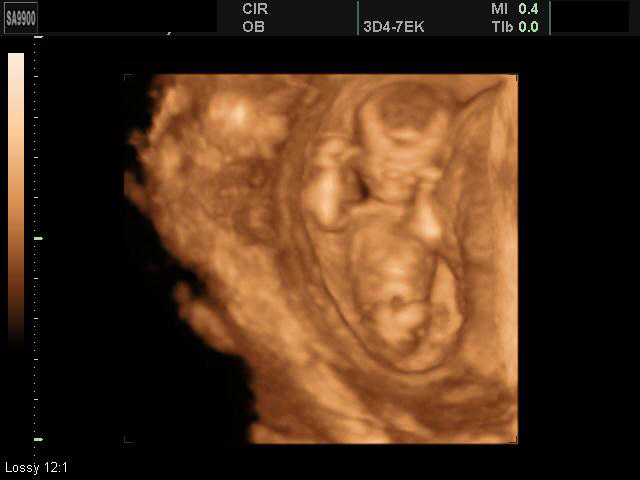

11-12 недель

12-13 недель

13-14 недель